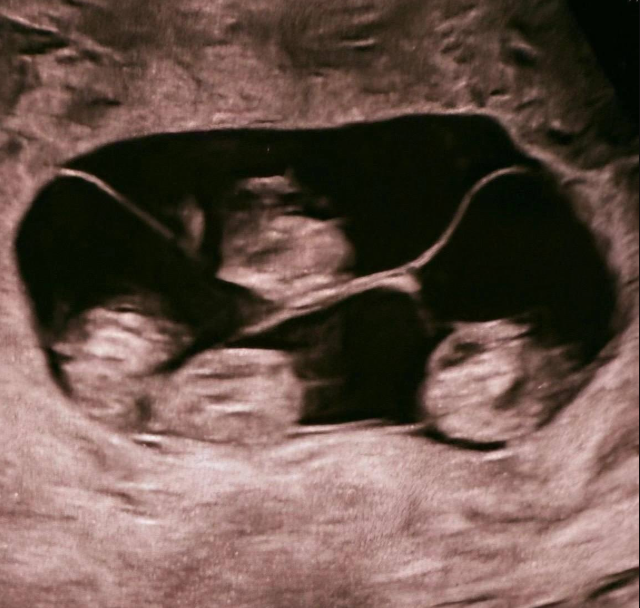

В Санкт-Петербурге зафиксирован уникальный для России случай - женщина родила однояйцевых четверняшек. Вероятность такого события оценивается примерно как один на 15,5 миллиона родов. На свет появились четыре полностью идентичные девочки, сейчас они находятся под наблюдением врачей. Подобные случаи крайне редки: во всём мире зарегистрировано около 15 таких рождений, и чаще всего это именно девочки. Рождение четверни считается событием экстра-класса, требующим слаженной работы большой медицинской команды.